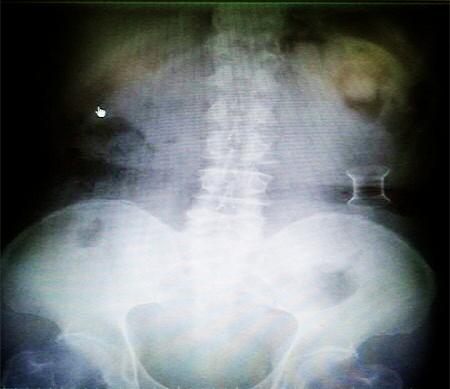

受試患者在結(jié)腸端端吻合術(shù)中,使用我司新研制產(chǎn)品達(dá)到了理想的預(yù)期效果?;颊咝g(shù)后7天、14天X光片顯影,可降解腸道支架均能按研制設(shè)計(jì)的預(yù)期時(shí)間節(jié)點(diǎn)保持應(yīng)有強(qiáng)度,術(shù)后21天X光片顯示可降解腸道支架已完全破碎,并排出體外。在整個(gè)試驗(yàn)過(guò)程中,病患無(wú)任何不良反映,耐受良好。